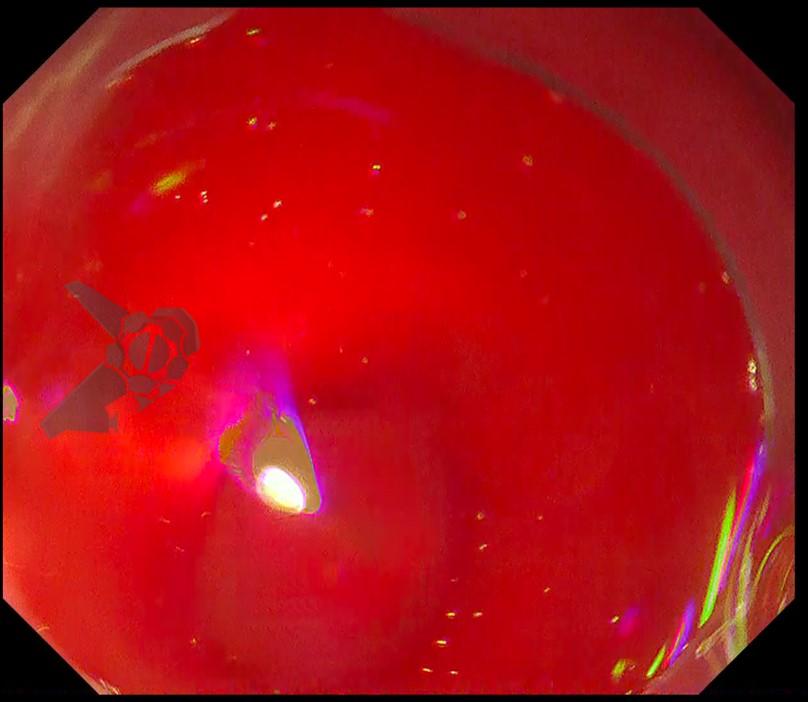

2. RDI (Red Dichromatic Imaging)

Essa tecnologia aplica os mesmos princípios do NBI, ou seja, são colocados filtros de luz. A diferença é que o RDI usa filtros de comprimentos de onda mais longos objetivando melhorar a visualização dos vasos mais profundos. As áreas com maior concentração de hemácias ficam com a cor laranja ou amarelo escuro, enquanto as áreas com menor densidade, ficam amarelas claras. Isso ajuda na hora de identificar o foco de sangramento ativo durante as ressecções endoscópicas (ESD ou mucosectomia), diminuindo o tempo para atingir uma coagulação adequada.

Fonte: Osaka International Cancer Institute.